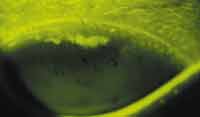

The lesions appear in the superior half of the cornea, very near or reasonably close to the limbus, and are arcuate in shape, hence the name of the condition. There is relatively little published data on this adverse event. It does not occur often; however, there is some suspicion that this problem may be more common with the new silicone hydrogel lenses. A recent poster presented at ARVO by O'Hare et al from the Cornea and Contact Lens Research Unit (CCLRU) in Sydney, Australia, indicates that SEALs form near the superior limbus with 71 percent occurring within 0.8mm of the limbus and 29 percent forming >0.8mm from the limbus.

Figure 1. Fluorescein stained Superior Arcuate Epithelial

Lesion. |

The cause of SEAL formation appears to be mechanical in origin. A tight peripheral geometry seems to be the main culprit with the contact lens impinging on and grinding away at the epithelium. SEAL location indicates that the presence of the upper lid probably contributes to the event. Some initially thought that hypoxia contributes to SEALs. I believe their continued presence with silicone hydrogels does not support this view. Temporary lens cessation will permit the lesions to heal, typically without sequelae. As mentioned, scarring is rare. Refitting to a flatter base curve and/or changing the lens material usually solves the problem. Using a "softer" lens may achieve the same effect.